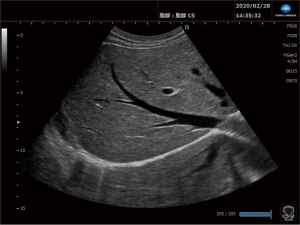

超音波検査(エコー)

当院では、超音波診断装置「SONIMAGE HS2PRO」を導入しています。

「プローブ」という専用器具で、人体に影響のない弱い超音波を体表から送受信することにより、臓器(肝臓、腎臓、膵臓、胆嚢、脾臓、等)や血流などをリアルタイムに診ることが出来る検査装置です。音波を画像にするので痛みもなく、安全で人に優しい検査装置です。